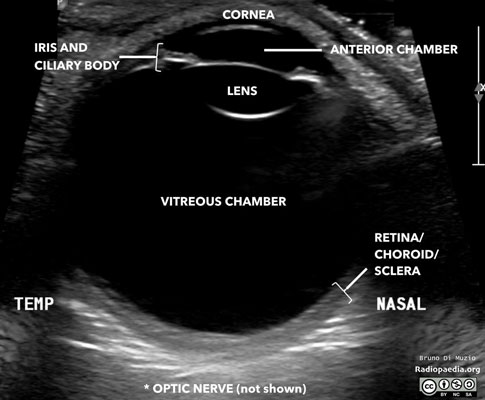

An eye and orbit ultrasound is a test to look at the eye area. It also measures the size and structures of the eye.

The test is most often done in the ophthalmologist's office or the ophthalmology department of a hospital or clinic.

Your eye is numbed with medicine (anesthetic drops). The ultrasound wand (transducer) is placed against the front surface of the eye.

The ultrasound uses high-frequency sound waves that travel through the eye. Reflections (echoes) of the sound waves form a picture of the structure of the eye. The test takes about 15 minutes.

Your eye is numbed, so you should not have any discomfort. You may be asked to look in different directions to improve the ultrasound image or so it can view different areas of your eye.